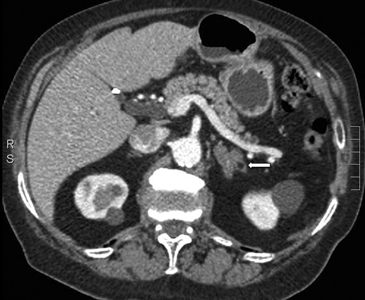

Las lesiones de mayor tamaño con frecuencia presentan componentes quísticos debido a necrosis central o hemorragia antigua (Figura 25 a, b, c y d).

Figura 25. Feocromocitoma quístico. Cortes axiales de resonancia magnética (a) ponderado en T2 secuencia HASTE y (b) ponderado en T1 con saturación grasa y uso de contraste ev. Se identifica una lesión sólido-quística suprarrenal derecha, marcadamente hiperintensa en secuencias ponderadas en T2 y con significativo refuerzo de sus septos con el uso de contraste. Otro caso (c) y (d) cortes axiales de TC donde se demuestra una lesión suprarrenal izquierda (flecha), que también presenta áreas hipodensas centrales determinadas por focos de degeneración quística.